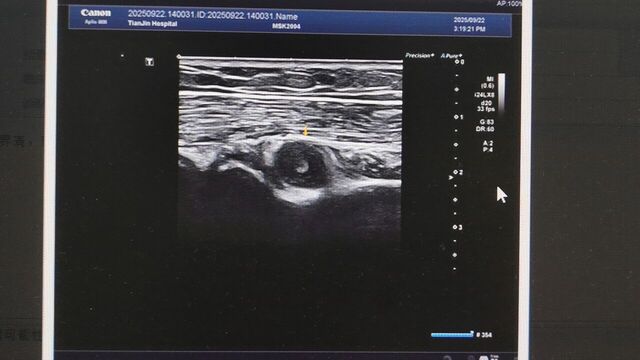

前臂近端背侧肿瘤,位于旋后肌内,紧贴桡骨颈部位

复习层次解剖: